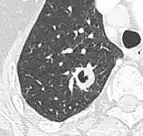

-

Low attenuating nodule (in this case a fat containing hamartoma).[9] -

Cavitation with relatively thick wall, in this case aspergilloma).[9]